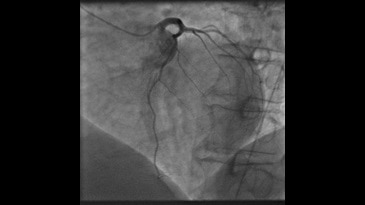

- InnovaSpin — оптимальная проекция сосуда за одну инъекцию контраста. Клиническое приложение для ротационной ангиографии Innova Spin позволяет увидеть всю камеру сердца и анатомию коронарных сосудов за одну съемку и с одной инъекцией контраста;